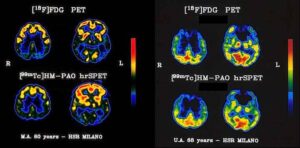

La somministrazione prolungata di immunoglobulina umana in modelli di malattia di Alzheimer si e' dimostrata efficace nel prevenire la malattia....